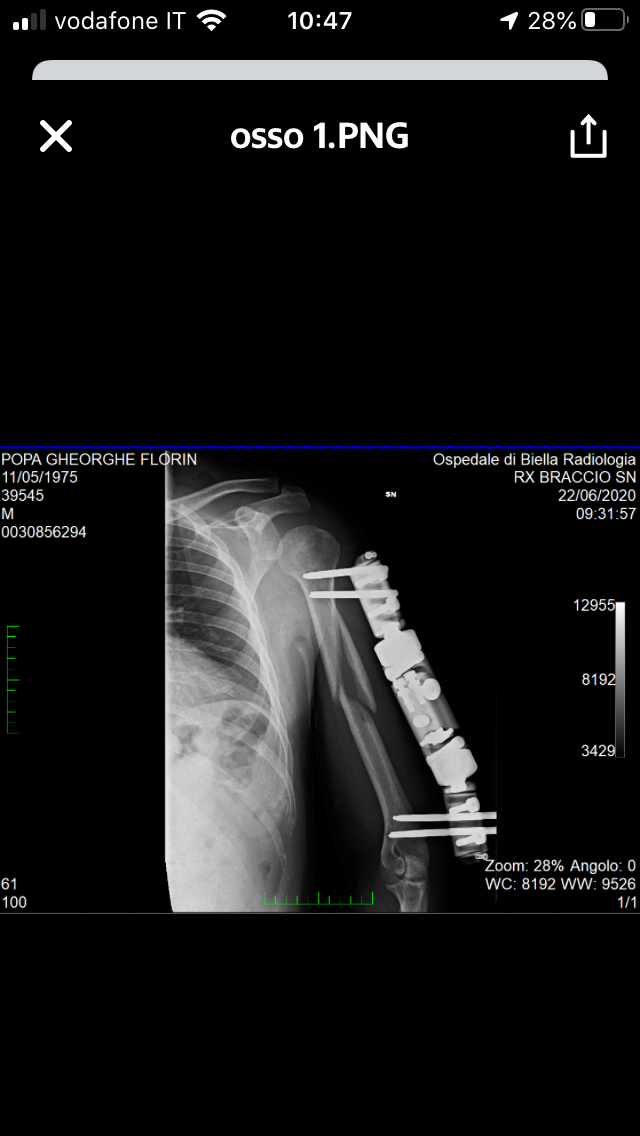

Buongiorno Dottore il 8 maggio sono stato sottoposto a un intervento per una frattura all’omero e mi hanno messo un fissatore esterno vorrei chiedere se è normale a tempo di due mesi che il calo osseo sia poco o quasi niente vorrei mandarli le radiografie fatte fino adesso grazie

Commento file: Questa è ultima radiografia